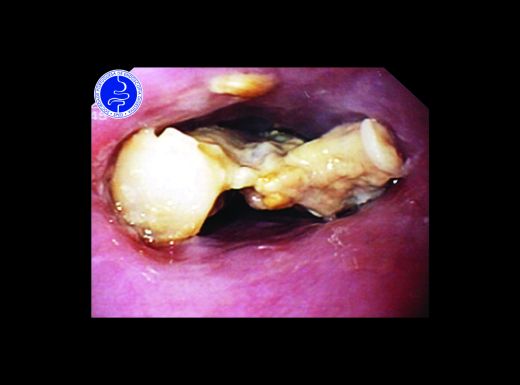

Corpo estranho - impacção alimentar